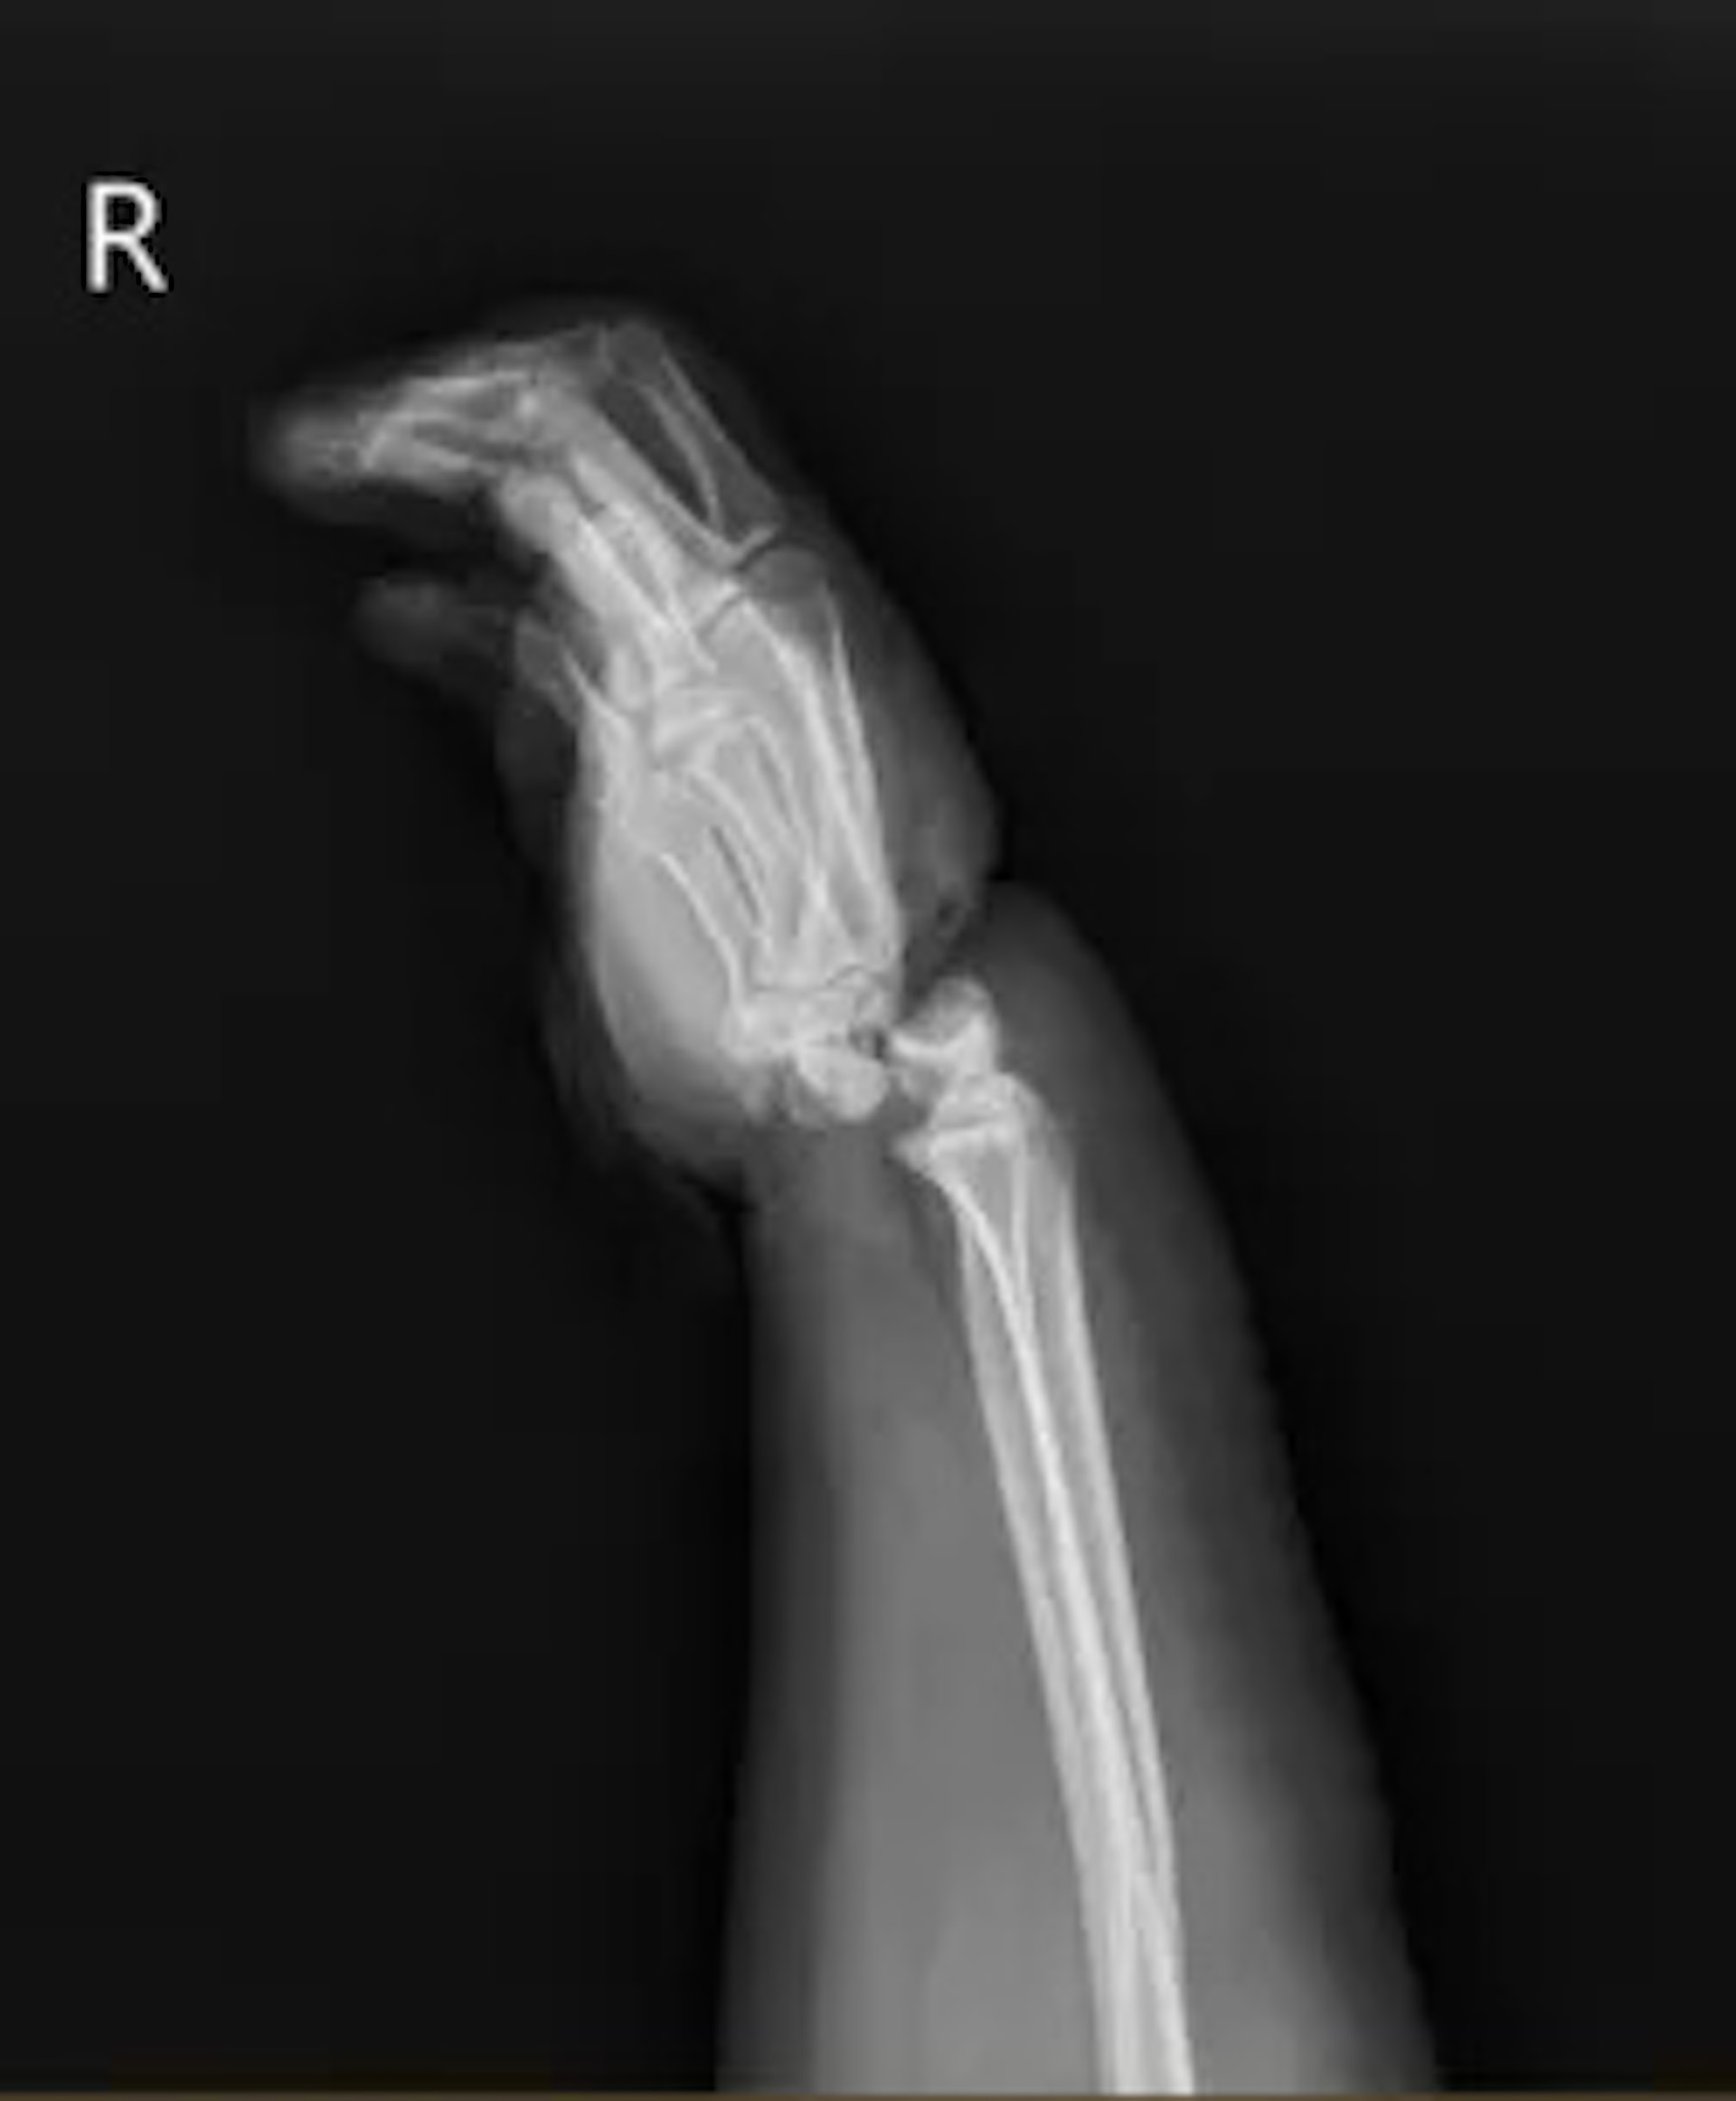

% u8 E6 j4 C, p! RX光片顥示,小美右手手腕嚴重變形。(澎湃新聞)公仔箱論壇$ S" {3 ~# i$ D8 E; }' a) |: j' W

& y: {/ u; c c2 M- ]公仔箱論壇寧波二院手顯微修復外科副主任郭宗慧介紹,小美入院時右手十分腫脹,手腕嚴重變形,被繩勒過的皮膚已壞死,手掌因缺血呈現青紫色。經檢查發現,小美的腕關節受暴力絞壓,兩條動脈血管已斷,並伴有長段血管損傷,靜脈血管出現長段栓塞,手腕關節已完全骨折脫位,有近1厘米寬的環形皮膚被擠壓壞死。

1 c7 w' u9 y( @* M# j- J- @來自浙江寧波的小美(化名),日前參加親子拔河比賽時,為更好地發力,便將麻繩繞在右手手腕上,未料雙方發力後,她的手腕被麻繩絞住。她被送至寧波市第二醫院時,腕關節已完全骨折脫位,被診斷為腕部離斷傷。醫院立即為她做手術,成功保住右手。